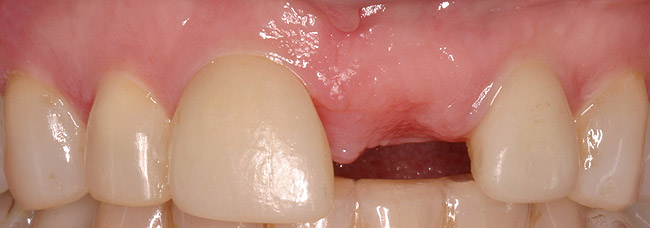

Figure 7a  Recently extracted tooth No. 9 (upper left central incisor), grafted site. Heavily treated adjacent teeth Nos. 8 and 10 with three-quarter porcelain laminate veneers.

Figure 7a

Figure 7b  Recently extracted tooth No. 9 (upper left central incisor), grafted site. Heavily treated adjacent teeth Nos. 8 and 10 with three-quarter porcelain laminate veneers.

Figure 7b